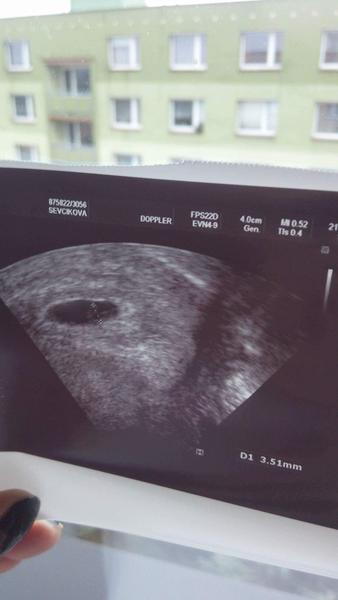

@lenka27 ahojky ja byla 7dni po vynechane ms a uz videt neco bylo 🙂

@bibinka2208 no, ale za 14 dni je uz i srdicko, spousta doktoru bere az po 14ti dnech vynechani pokud teda nejsou nejake obtize samozrejme

Ahoj holky, tak ms nedorazila 😉 14.1. jdu k lekari, tak mi drzte palecky prosiim)

Jojo, ja byla na prvni kontrole az vlastne v 7 tt a bylo i srdicko 🙂 ale volala jsem hned,abych se mela na kdy tesit 🙂